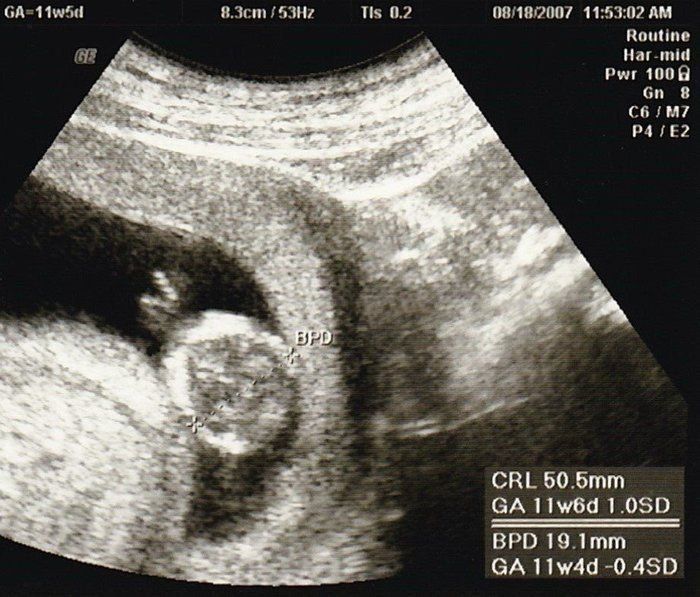

命の始まりは神秘的!2D・3D・4Dのエコー写真で見る「私と赤ちゃんの実録260日」 -

緊急帝王切開で誕生。エコー写真で綴る息子と過ごした252日 -